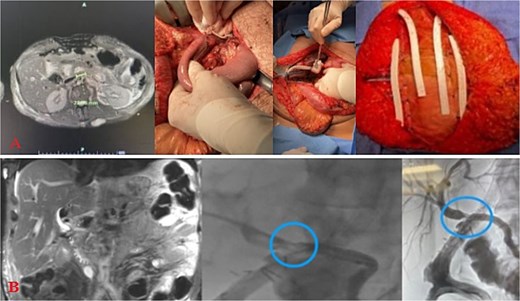

The patient stayed a total of 77 days at the hospital with around 54 days spent in the ICU. He was initially in ICU care for his extensive traumatic and complicated recovery. On POD1–3 increased bilious output was noted from a JP drain. He was taken back to the operating room (OR) on POD3 for re-exploration. There was a small contained biliary collection of ~2.23 cm in the GB fossa without active bile leak noted, viable bowel, and intact duodenal repair. The patient underwent placement of a gastrostomy and feeding jejunostomy tubes, an appendectomy, and abdominal wall reconstruction with Ovitex. He returned to the OR on POD7 for frank blood noted in another JP drain where a persistent gush of blood was noted at the GB fossa. This was repaired with multiple clips and figure of 8 sutures. The abdomen was packed and the Abthera wound vac was replaced. Repeat re-exploration on POD8 noted continued hemostasis, but there remained bile near the porta hepatis and two additional JP drains were left in the region of concern. He recovered well for the consequent days with stabilized bilirubin levels (Fig. 2A). However, on POD20, it was noted that he had increasing bile output of over 1 L over 24 hours. The bile was consequently fed back through his J-tube, and on POD25, a hepatobiliary iminodiacetic acid scan (HIDA) scan failed to demonstrate the leak and an initial ERCP attempt failed secondary to a duodenal diverticula. On POD27, magnetic resonance cholangiopancreatography (MRCP) demonstrated a common hepatic duct stricture. ERCP was successful in cannulation of the ampulla on POD32 with continued lack of contrast extravasation at the distal common bile duct. On POD35, percutaneous transhepatic cholangiography drain was placed to relieve concerns of a leak. On POD54, interventional radiology and gastroenterology successfully completed a ERCP rendezvous procedure to place a biliary stent over the area of stricture. (Fig. 2B) This intervention successfully reduced the amount of bilious and overall JP output. On hospital Day 77, he was consequently discharged with all drains removed and tolerating a regular diet.

Injury sequelae and interventions. A: Re-exploration due to bilious changes. B: Delayed presentation of common hepatic duct stricture with rendezvous procedure.